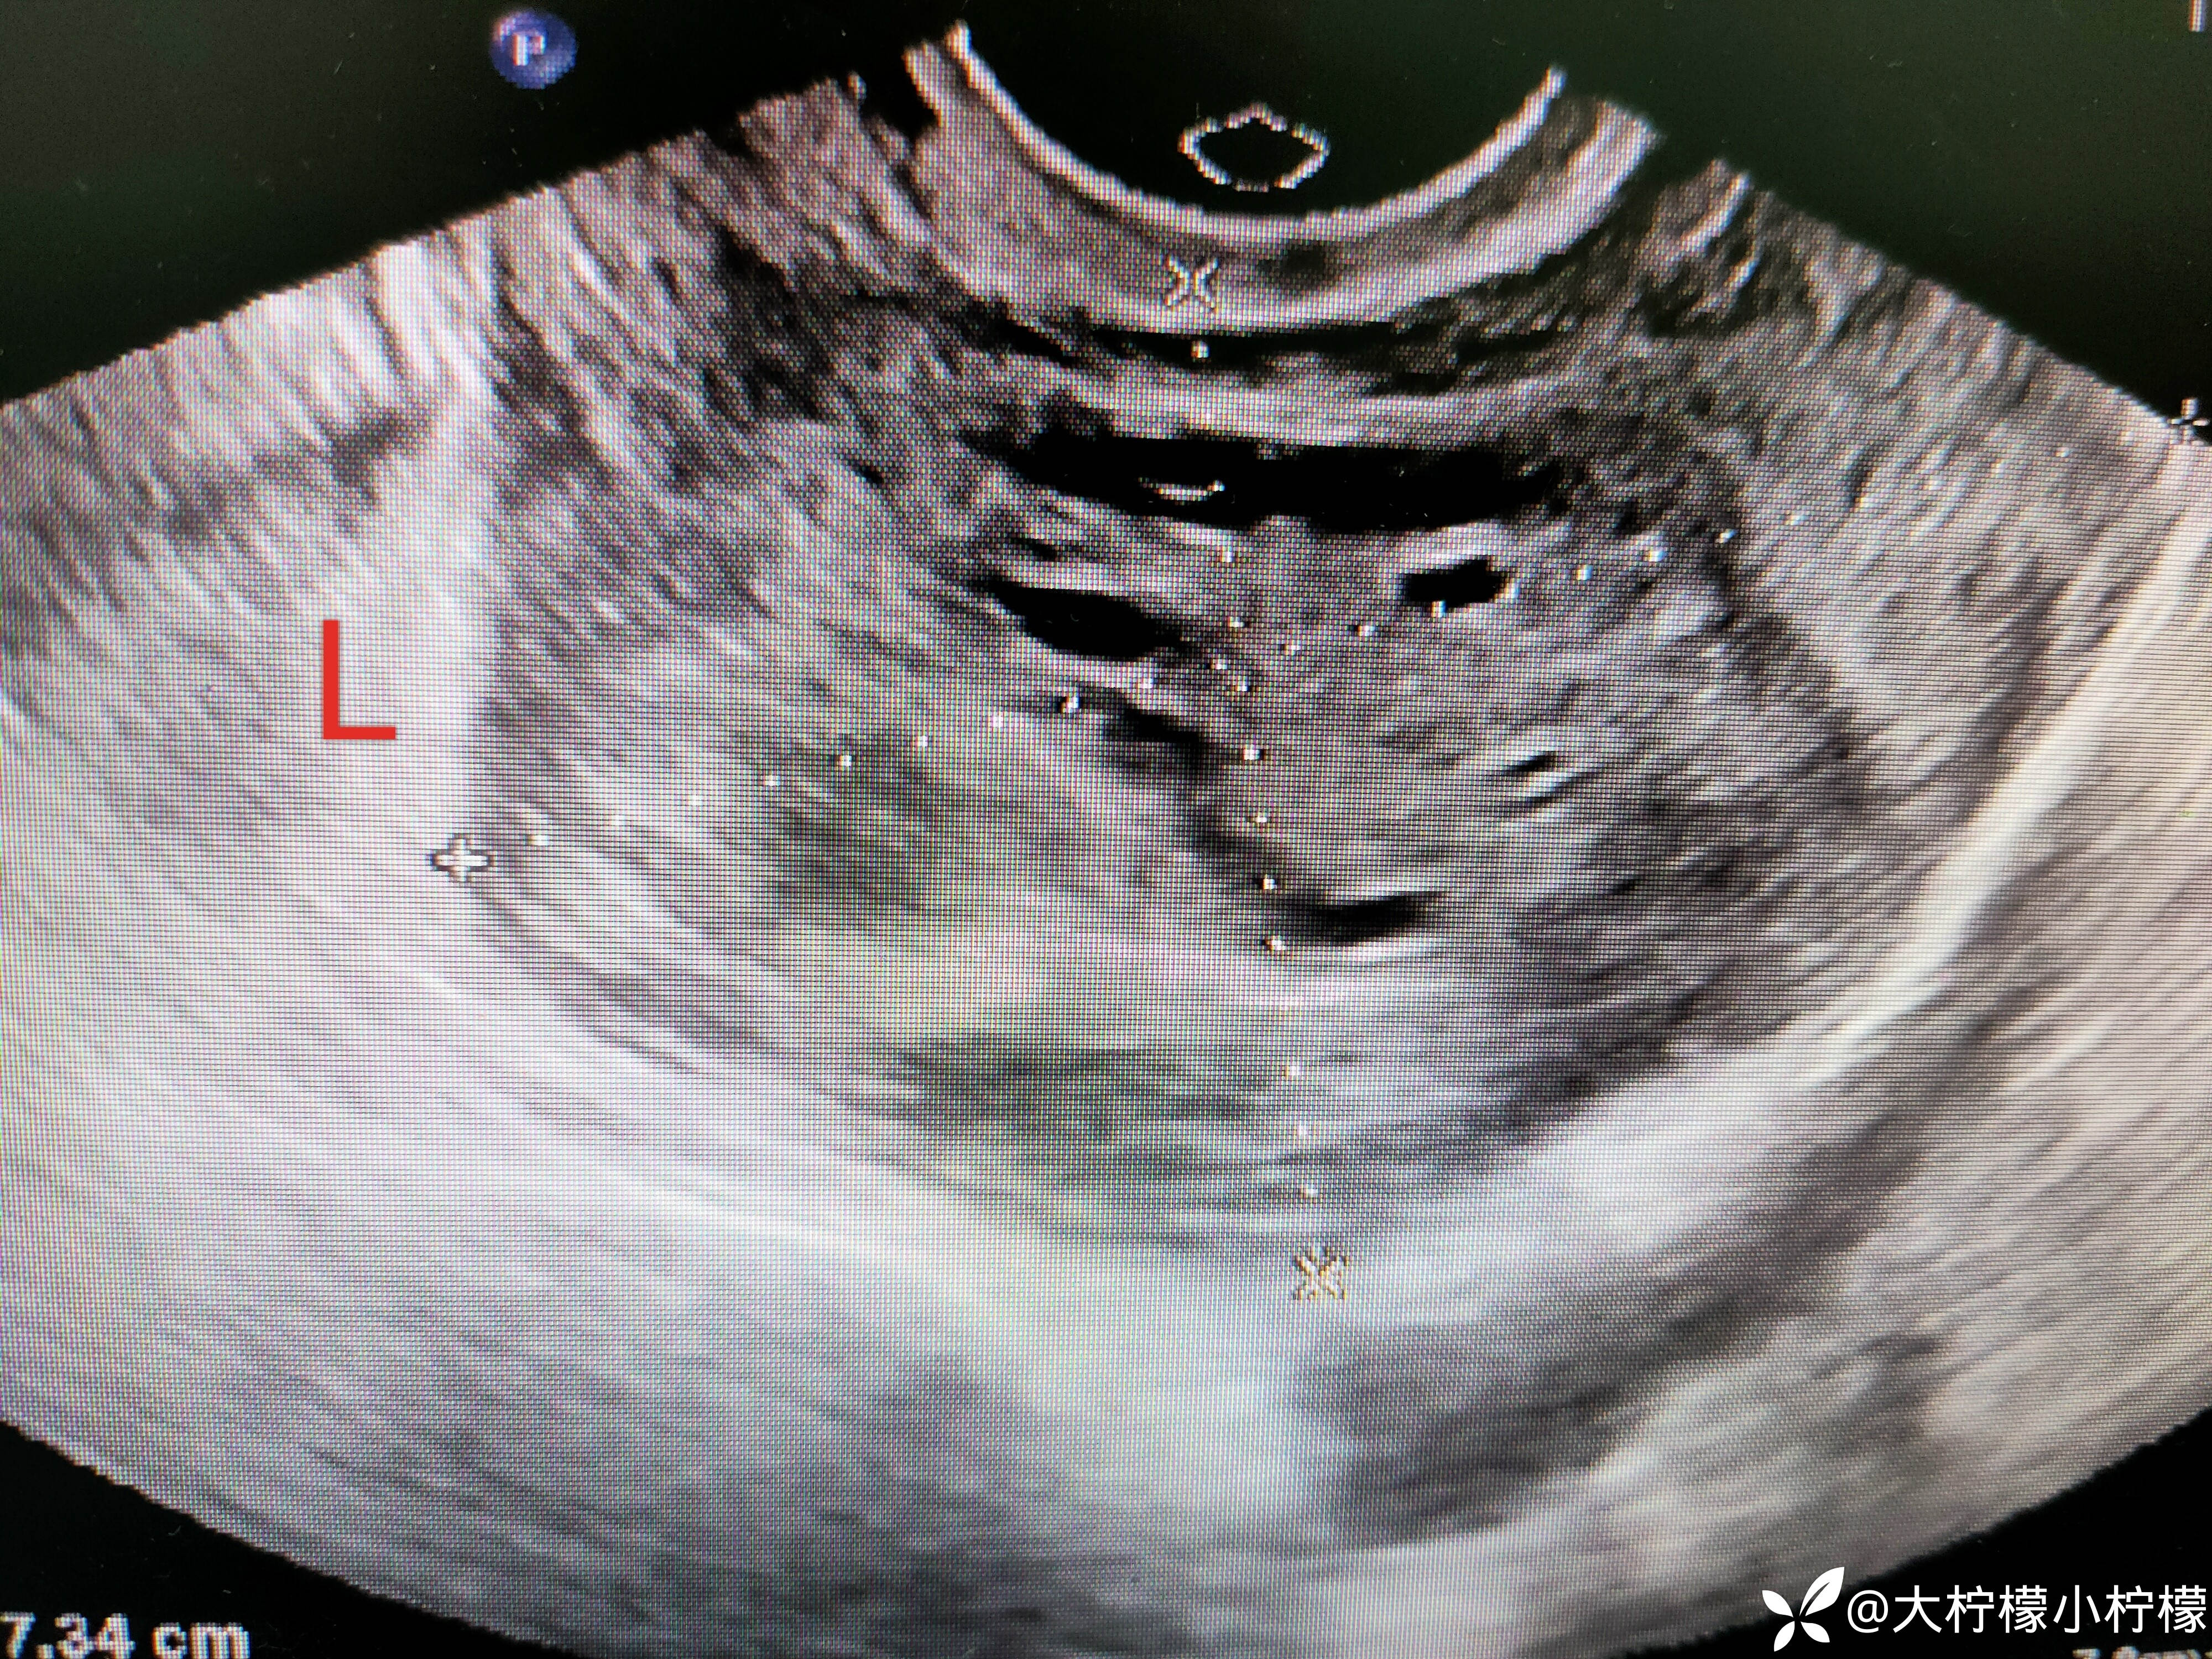

简要病史:患者年轻女性,平素月经周期规律,6-7/30余天,末次月经2023年10月16日,月经量正常,有痛经史,8小时前同房后出现左侧下腹部疼痛,呈持续,急诊超声:如下:

左附件区不均质回声,卵巢被包裹在内。